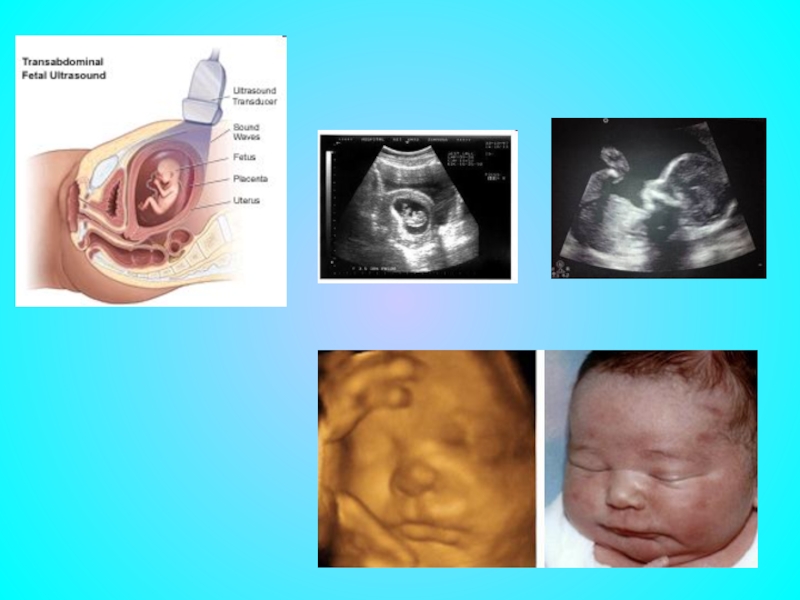

Слайд 23Неинвазивные методы

– это методы обследования плода без оперативного вмешательства. В настоящее

время к ним относится только ультразвуковое исследование .

Слайд 24УЗИ во время беременности является скрининговым методом обследования, т.е. оно проводится

в обязательном порядке у каждой беременной женщины. Согласно приказу министерства здравоохранения РФ № 457 «О совершенствовании пренатальной диагностики в профилактике наследственных и врожденных заболеваний у детей» утверждено трехкратное скрининговое ультразвуковое исследование:

первое в сроках от 10 до 14 недель;

второе – от 20 до 24 недель;

третье — от 32 до 34 недель.